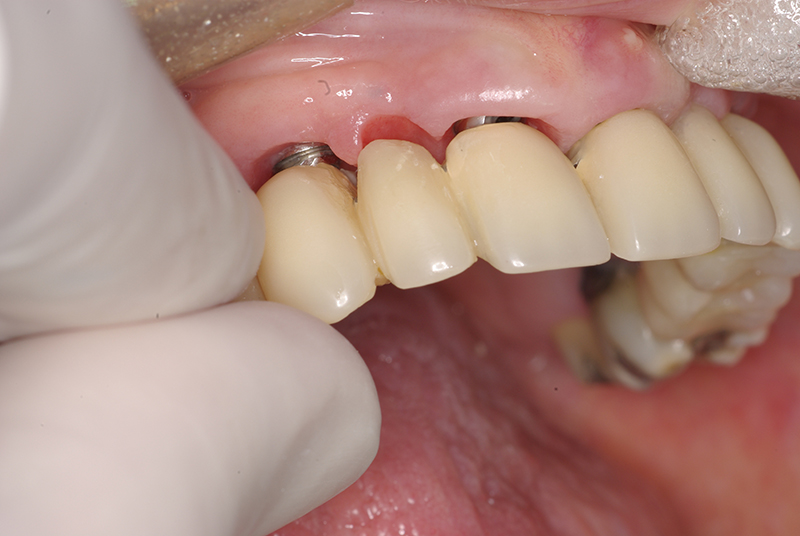

Na Clínica Pontes Odontologia, somos referência em implantes dentários em Fortaleza, oferecendo tratamentos de alta qualidade e tecnologia de ponta. Os implantes dentários são estruturas de titânio posicionadas cirurgicamente no osso maxilar ou mandibular para substituir as raízes dos dentes ausentes. Essa técnica permite a fixação de próteses personalizadas, restaurando a função mastigatória, a estética e a autoestima dos nossos pacientes.

Utilizamos a tecnologia CAD CAM, um sistema avançado que possibilita a confecção precisa das próteses dentárias diretamente sobre os implantes. Esse método inovador garante um ajuste perfeito, um resultado estético superior e proporciona muito mais conforto e durabilidade. Com o CAD CAM, nossos pacientes contam com um processo mais rápido e previsível para alcançar o sorriso desejado.